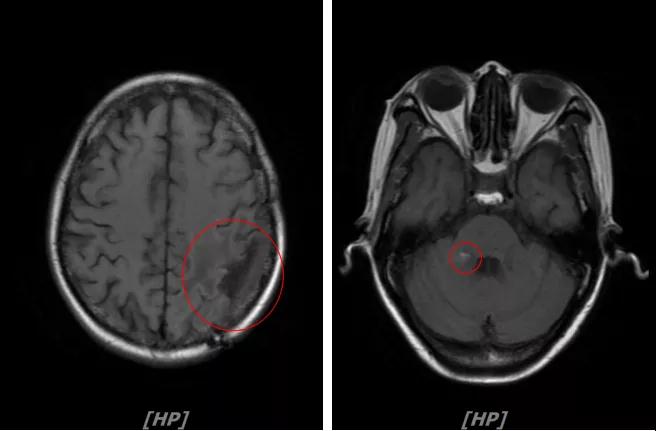

b.2014年3月全脑放疗结束后,予以LX方案治疗(拉帕替尼 1250mg qd+卡培他滨 1500mg bid)。每3个月规律复查,未见明显异常。下图为2014年6月患者行头颅增强MR检查,提示左顶叶脑转移瘤术后改变。

每3个月规律复查,未见明显异常。如2015年8月 头颅MR检查,提示:左顶叶脑转移瘤术后放疗后改变,对比前片2015年3月10日相仿。

头颅增强MR:左侧顶枕叶见片状T1WI低信号、T2WI高信号影,增强后病灶边缘见局部斑片状强化改变,邻近脑膜轻度强化改变;右侧脑室三角区内侧见大小约8x14mm的结节影,T1WI低信号、T2WI等高信号,增强明显强化,灶周水肿明显;两侧脑室旁见片状异常信号,T1WI低信号,T2WI高信号,增强未见明显强化,余脑室、脑池、脑沟大小形态可,中线结构居中无移位

左顶叶脑转移瘤术后放疗后,左顶叶术区边缘强化灶;考虑肿瘤复发

右侧脑室三角区内侧转移瘤

两侧脑室旁云絮状异常信号,考虑放疗后改变